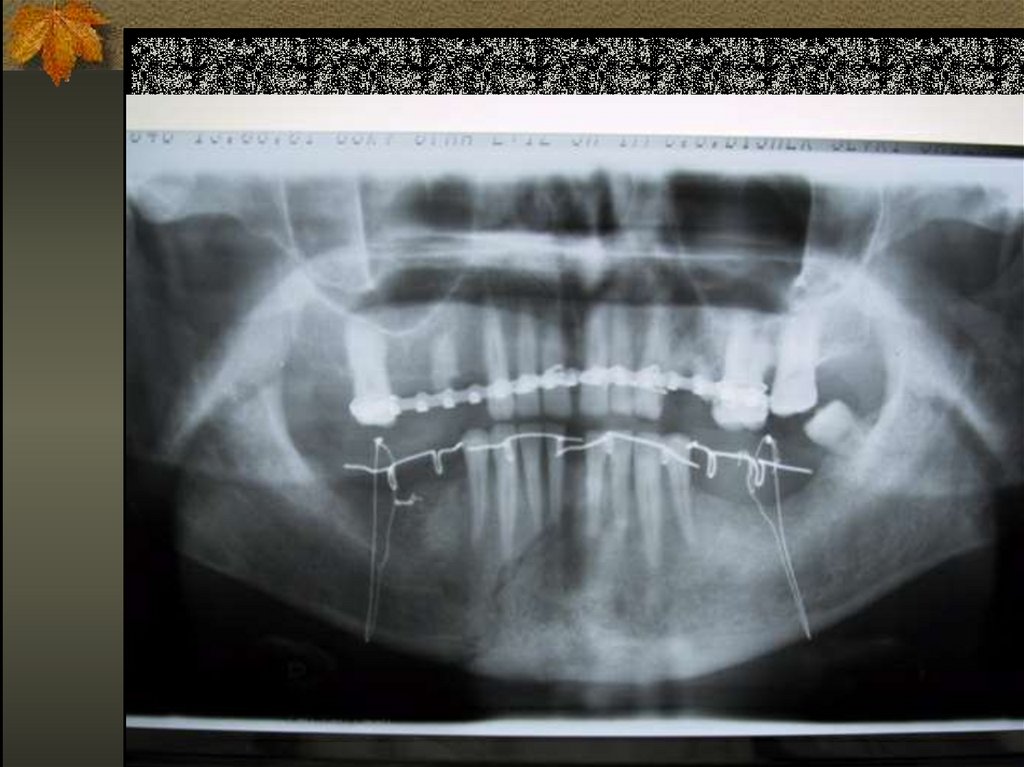

11. Vestibüler arklar (şineler)(ateller)

Ateller, fragmanları ve çeneleri aynı

anda birbirine birleştirmek maksadıyla

uygulanır. Aparey diş kavsinin

uzunluğunca devam eder devamlılık

lingual ve vestibül yüzdede aynıdır.

Ateller dişlere ligatürler vidalar veya

bilezikler yardımıyla bağlanır.

12. ateller

Hijyenik bakımın zorluğu, beslenme

güçlükleri, genel anestezi altında

uygulanmasının imkansızlığı, dişsiz

veya az sayıda dişli olanlara

uygulanamaması dezavantajlarıdır.

Atellerle çeneler arası blokajda iyileşme

dişlerin karşılıklı temaslarının

mükemmelliği oranında tatminkardır.